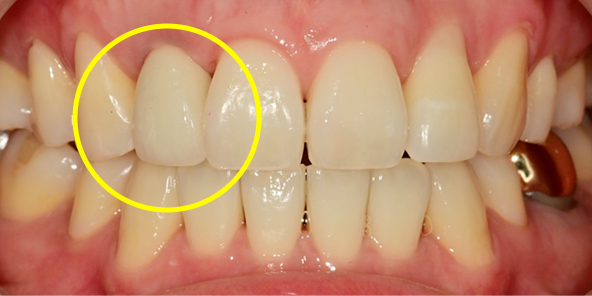

치료 전

임플란트 최종 결과

BEFORE/AFTER

BEFORE

AFTER